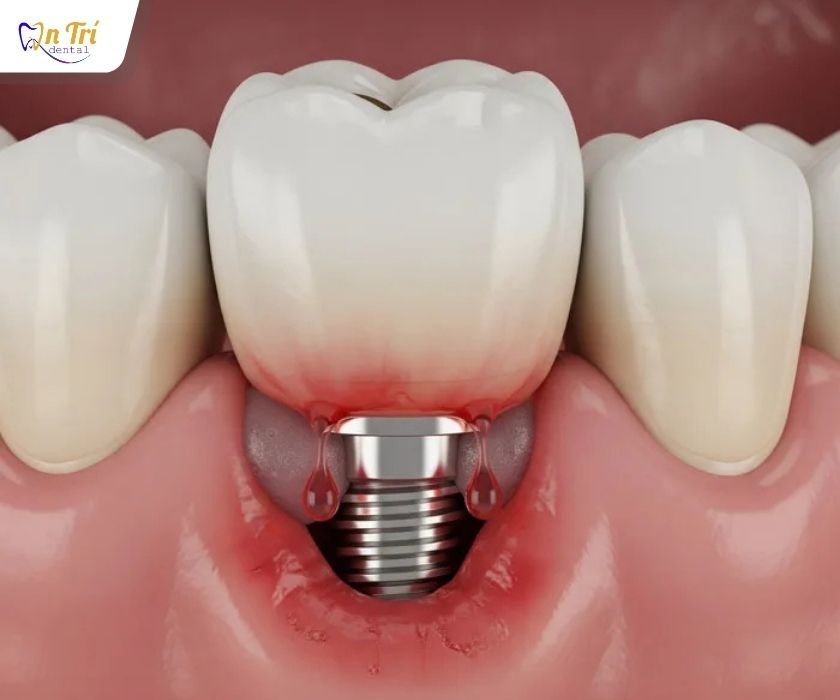

Implant nha khoa là một trụ kim loại sinh học, thường làm từ Titanium hoặc hợp kim Titanium, được đặt trực tiếp vào xương hàm để thay thế cho chân răng đã mất. Sau khi tích hợp vững chắc với xương, Implant đóng vai trò như một nền móng nâng đỡ cho răng phục hình bên trên.

Một hệ thống Implant hoàn chỉnh bao gồm ba thành phần chính. Phần thứ nhất là trụ Implant nằm trong xương hàm, chịu trách nhiệm truyền lực nhai. Phần thứ hai là khớp nối trung gian, giúp kết nối trụ Implant với mão răng bên trên. Phần thứ ba là mão răng sứ hoặc phục hình toàn hàm, đảm nhiệm chức năng ăn nhai và thẩm mỹ.

Máng phẫu thuật giúp implant được đặt chính xác vào xương hàm

Máng phẫu thuật giúp implant được đặt chính xác vào xương hàm